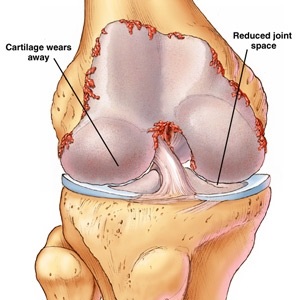

Care sunt simptomele de tendinită a genunchiului? A se vedea aici.